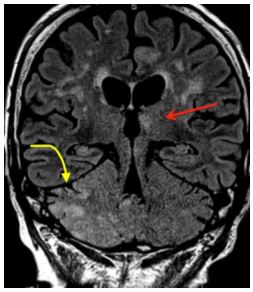

MR imaging of the brain demonstrated restricted diffusion and abnormal gyriform FLAIR signal involving the left frontal lobe, affecting the cingulate, inferior and middle frontal gyri and the frontal operculum (Figure 1a and b). Coronal FLAIR sequences demonstrated additional areas of abnormal signal in the left anteromedial thalamus and portions of the striatum; these areas, unlike the left frontal cortex, did not demonstrate corresponding restricted diffusion (Figure 2). In addition to the left frontal cortex, restricted diffusion and bright signal on FLAIR were observed in the right cerebellum, affecting the tonsil, the cerebellar folia and inferior segments of the vermis, including the tuber, pyramis, and uvula (Figure 2 and 3). No pathologic enhancement was demonstrated. The cortical restricted diffusion was compatible with seizure edema and the contralateral cerebellar diffusion restriction was attributable to crossed cerebellar diaschisis caused by seizure edema.

| Figure 2: Seizure related changes in the deep grey nuclei. Coronal FLAIR sequences of the brain demonstrate abnormal signal within the left anteromedial thalamus and portions of the striatum (straight arrow). No associated restricted diffusion was demonstrated. Extensive signal abnormality is seen in the right cerebellar hemisphere, compatible with CCD (curved arrow) |